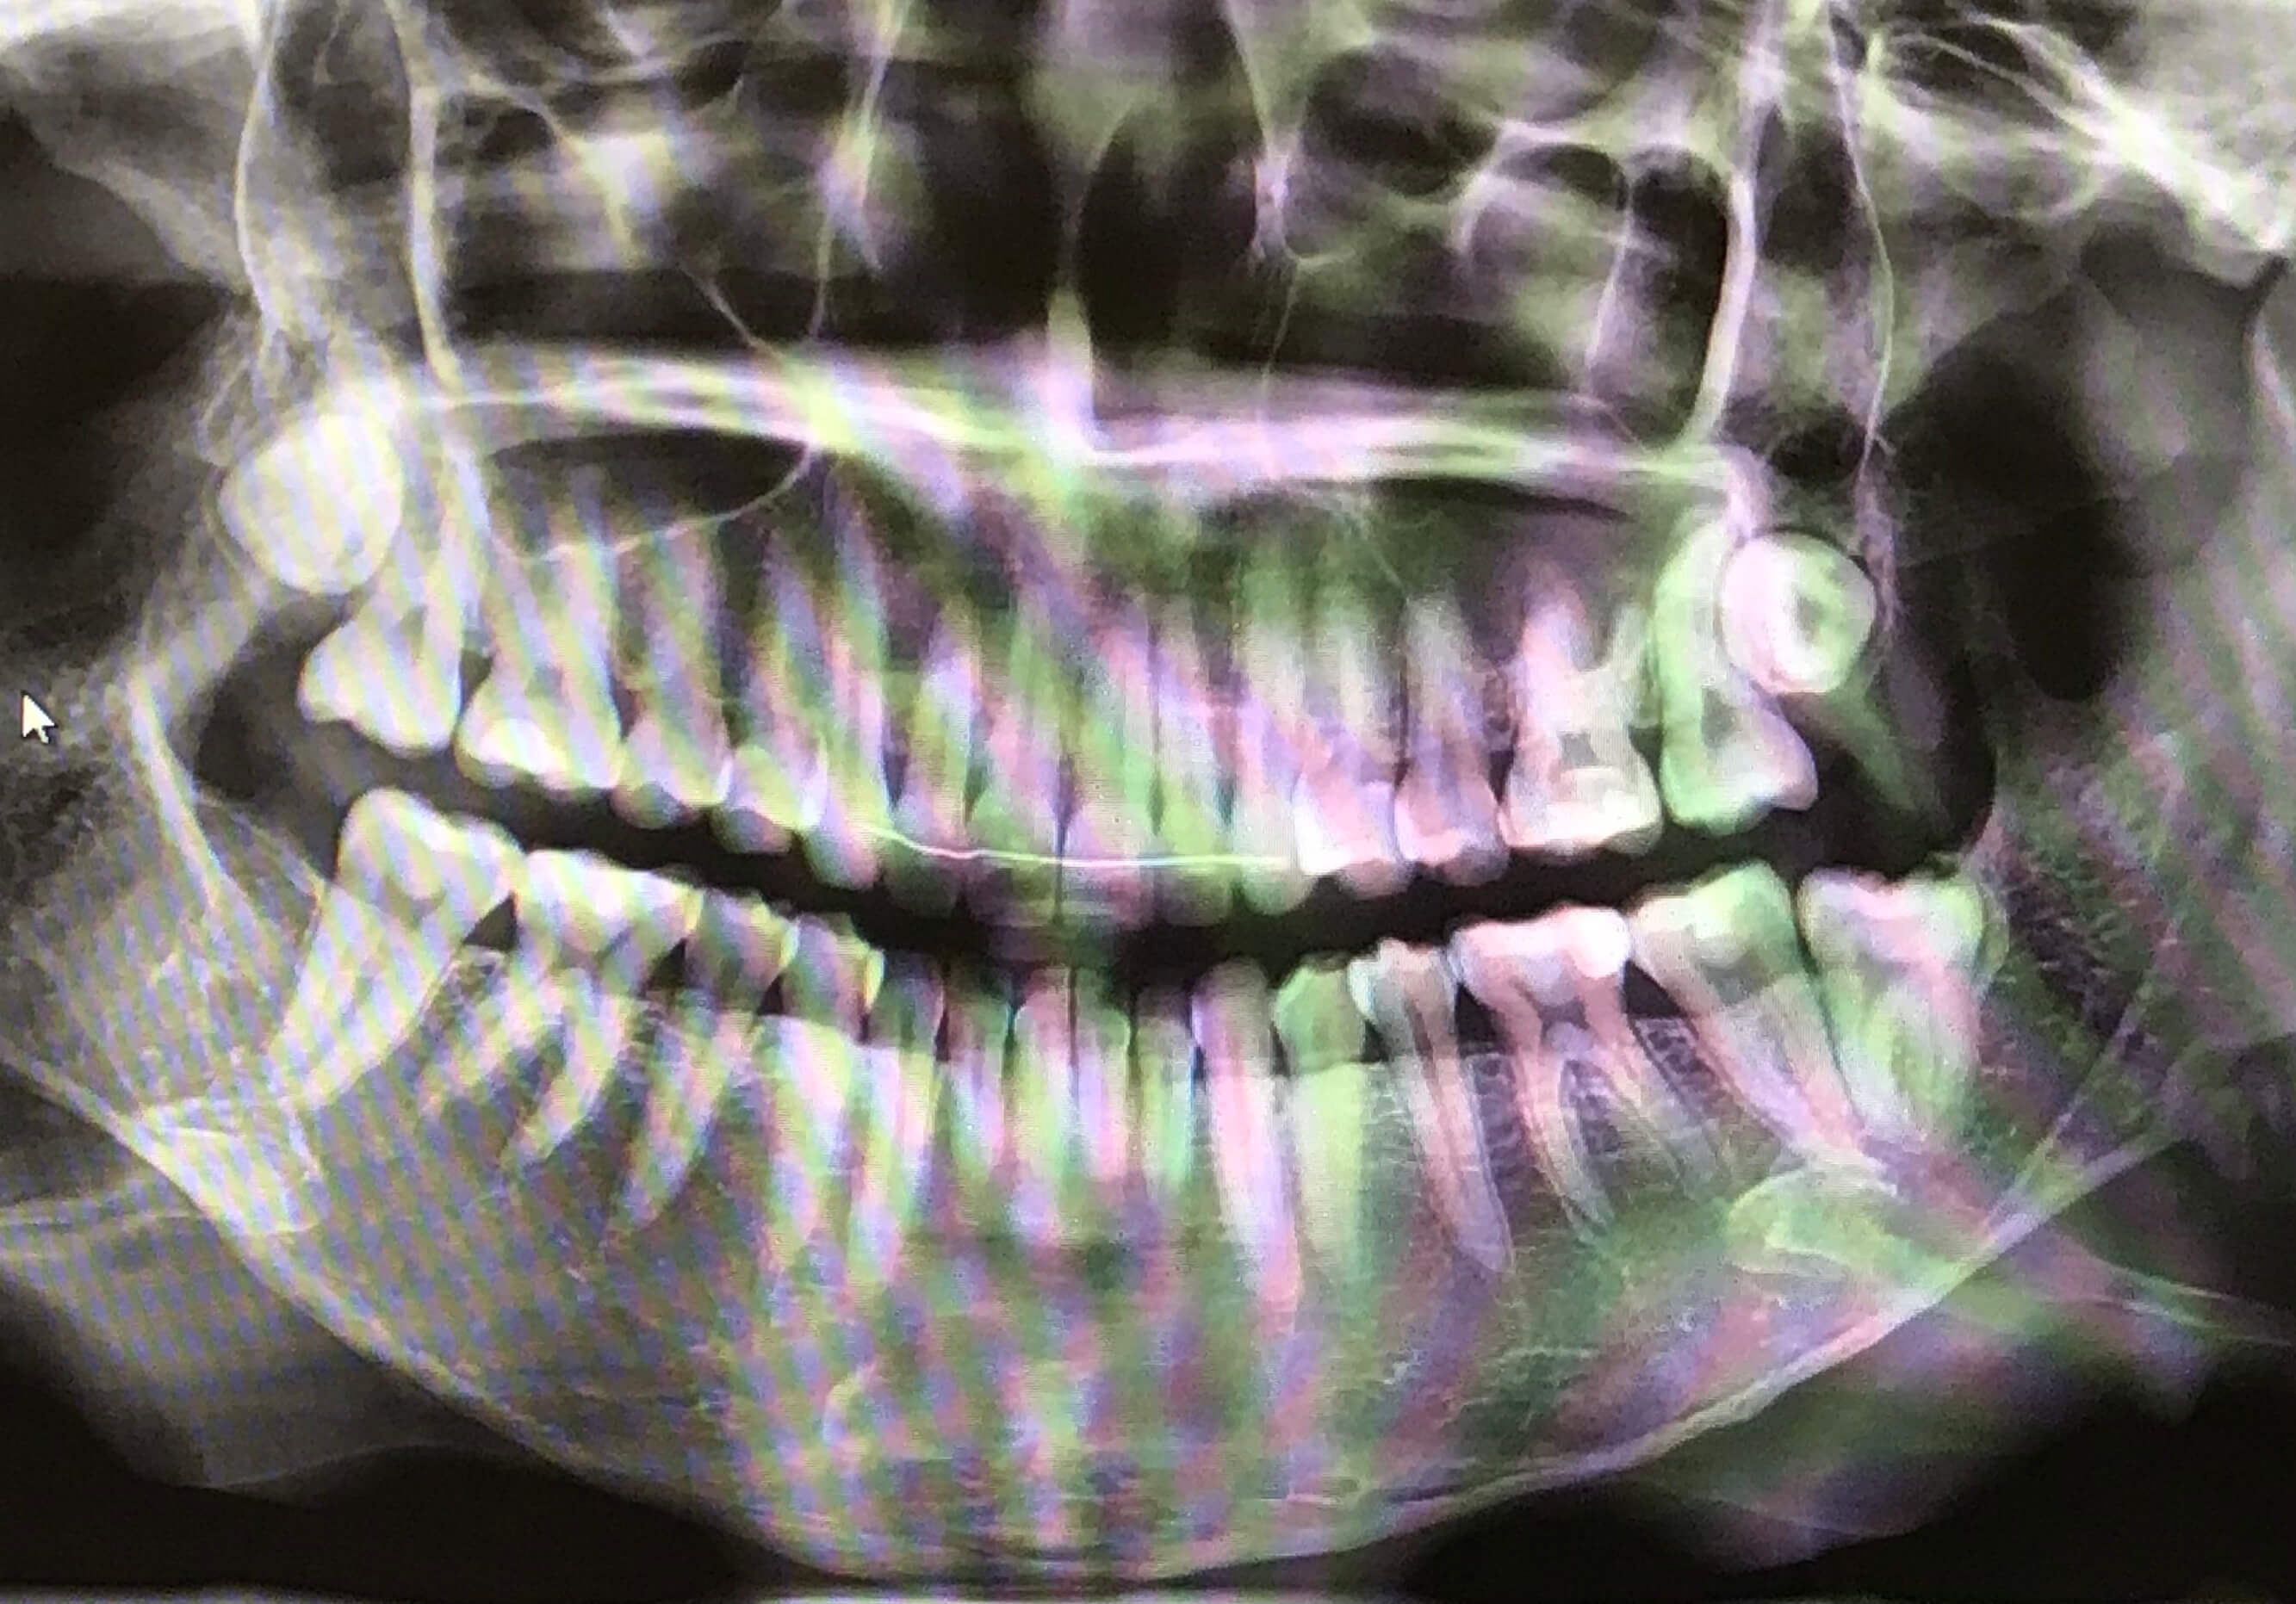

저는 총 4개의 사랑니 위아래로 나 있었고

위 사랑니는 바르게 나 있고 나오지 않은 상태입니다

아래 사랑니 1개는 옆으로 기울어져 나와 있어서 20대 초반에 뽑았습니다 문제는...

남은 아래 사랑니 였는데요 바르게 났지만 반만 나온 상태였습니다.

사랑니가 살짝 나온 상태라서 잇몸을 째고 치아를 부셔서 뺀다고 했어요